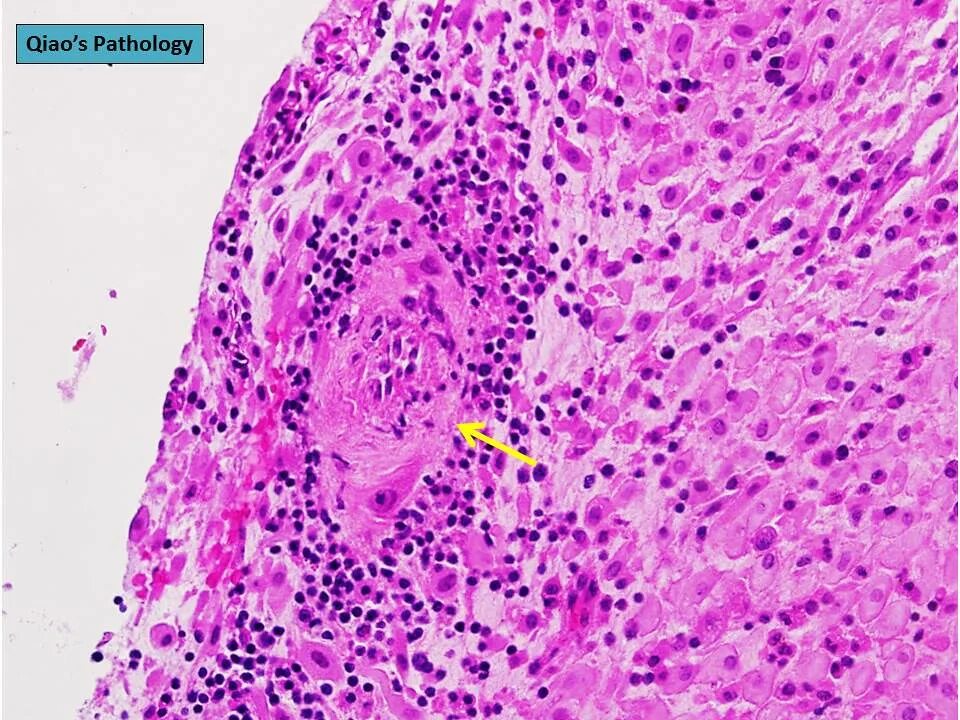

Некроз тканей соприкасающихся с внешней средой называется